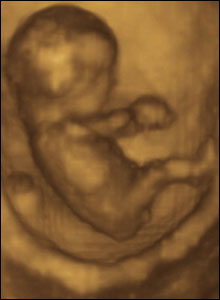

8 týdnů, 40 mm

V osmi týdnech života je plod schopný kopat a natahovat nohy, točit s nimi a zvedat ruce nahoru a dolů.